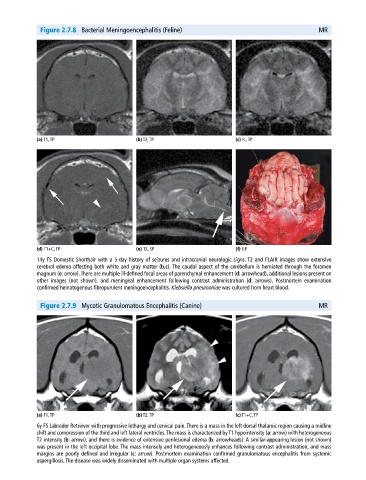

Figure 2.7.8 Bacterial Meningoencephalitis (Feline) MR

(a) T1, TP (b) T2, TP (c) FL, TP

(d) T1+C, TP (e) T2, SP (f) GP

14y FS Domestic Shorthair with a 5‐day history of seizures and intracranial neurologic signs. T2 and FLAIR images show extensive

cerebral edema affecting both white and gray matter (b,c). The caudal aspect of the cerebellum is herniated through the foramen

magnum (e: arrow). There are multiple ill‐defined focal areas of parenchymal enhancement (d: arrowhead), additional lesions present on

other images (not shown), and meningeal enhancement following contrast administration (d: arrows). Postmortem examination

confirmed hematogenous fibropurulent meningoencephalitis. Klebsiella pneumoniae was cultured from heart blood.

Figure 2.7.9 Mycotic Granulomatous Encephalitis (Canine) MR

(a) T1, TP (b) T2, TP (c) T1+C, TP

6y FS Labrador Retriever with progressive lethargy and cervical pain. There is a mass in the left dorsal thalamic region causing a midline

shift and compression of the third and left lateral ventricles. The mass is characterized by T1 hypointensity (a: arrow) with heterogeneous

T2 intensity (b: arrow), and there is evidence of extensive perilesional edema (b: arrowheads). A similar‐appearing lesion (not shown)

was present in the left occipital lobe. The mass intensely and heterogeneously enhances following contrast administration, and mass

margins are poorly defined and irregular (c: arrow). Postmortem examination confirmed granulomatous encephalitis from systemic

aspergillosis. The disease was widely disseminated with multiple organ systems affected.